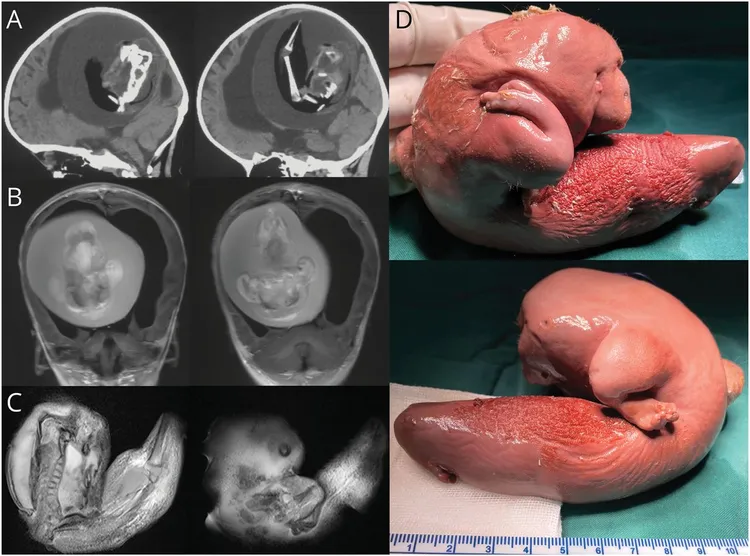

根據美國《邁阿密先鋒報》9日報導,中國一名1歲女嬰被發現行動功能出現問題,頭部變大,且發育速度沒有達到同齡嬰孩的預期水平。醫生仔細評估,對她的頭部進行X光檢查時,在其腦部看到一個囊塊,且裡面有骨頭。

專家指出,這個現象為腦室內胎中胎。研究報告發表在知名期刊《神經病學》(Neurology)。

手術後取出的確實是一個胎兒,長約10公分,其手臂和手掌可看出已經形成。這個胎中胎有脊椎,但仍屬未發育;醫師稱此為「胚樣」,是一種類似胎兒的生長。

醫師對這個胎中胎進行DNA檢測後,確認是1歲女嬰的雙胞胎,研判是在大腦和脊髓組成必需步驟的「神經板摺疊」發育過程期間,被吸收掉;這或許可以解釋寄生胎如何最終進入她的顱骨裡。